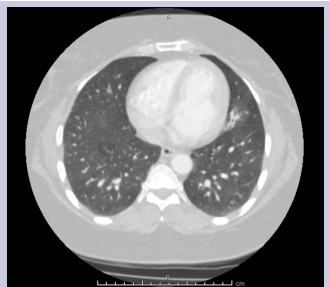

Diagnostic work up showed white blood cell count 7.3, hemoglobin 11.8, platelets 210, and erythrocyte sedimentation rate 30. AFB sputum was negative; legionella urine antigen was negative, blood cultures were negative, INR was 0.9. Non-contrast transthoracic echocardiogram was normal. There was no evidence of shunt on the two-dimensional transthoracic echocardiogram bubble study. Computed tomography of the chest revealed focal opacity in the inferior segment of the lingula [Figure 1 & 2].

Figure 1: CT Thorax showing a focal opacity involving the left lingula